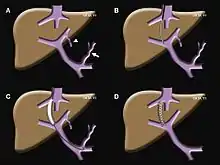

Transjugular intrahepatic portosystemic shunts are typically placed by an interventional radiologist under fluoroscopic guidance.[9] Access to the liver is gained, as the name 'transjugular' suggests, via the internal jugular vein in the neck. Once access to the jugular vein is confirmed, a guidewire and introducer sheath are typically placed to facilitate the shunt's placement. This enables the interventional radiologist to gain access to the patient's hepatic vein by traveling from the superior vena cava into the inferior vena cava and finally the hepatic vein. Once the catheter is in the hepatic vein, a wedge pressure is obtained to calculate the pressure gradient in the liver. Following this, carbon dioxide is injected to locate the portal vein. Then, a special needle known as a Colapinto is advanced through the liver parenchyma to connect the hepatic vein to the large portal vein, near the center of the liver. The channel for the shunt is next created by inflating an angioplasty balloon within the liver along the tract created by the needle. The shunt is completed by placing a special mesh tube known as a stent or endograft to maintain the tract between the higher-pressure portal vein and the lower-pressure hepatic vein. After the procedure, fluoroscopic images are made to show placement. Pressure in the portal vein and inferior vena cava are often measured.